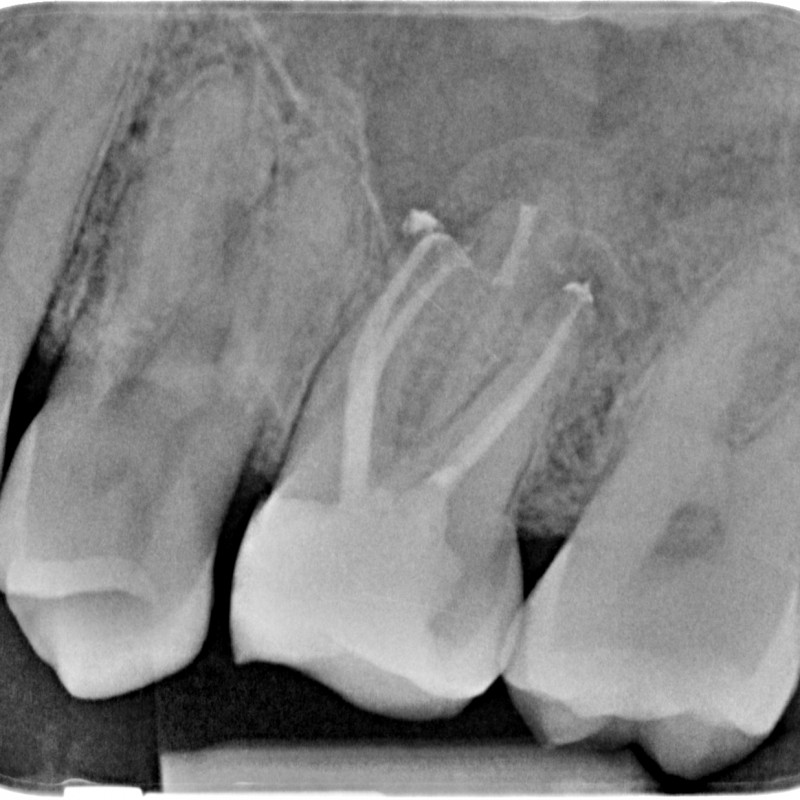

721106-07-5220-X-20150521-145313-XCSP0ZO8VCHE-3